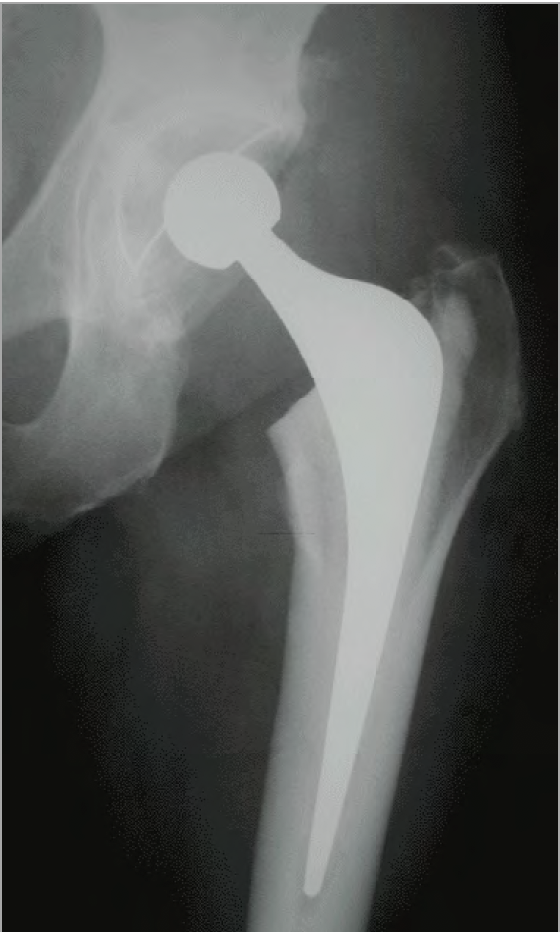

A Total Hip Replacement involves the removal of a painful Hip Joint and replacing it with a new ball and socket into the arthritic hip joint, helping relieve hip pain and resume mobility. The procedure is usually conducted under a spinal anaesthetic, but it can be combined with some sedation so that you are effectively asleep.

Once the joint capsule has been opened, the hip is popped out of the socket, and the worn head of the femur is removed. The acetabulum or socket is then prepared with special instruments that scrape off any remaining cartilage. The new cup is inserted, and this can be either pressed in, secured with screws or cemented in place. The space down the femur bone is then enlarged to accept the new femoral component, and it can also be pressed in or cemented into place. The new head fits on to the femoral component, and the hip is reduced back into the socket. Final checks for length and stability are made, and any muscles that were released are then repaired, and the wound is closed.

- If you have not had an x-ray in the recovery room then you will have an x-ray taken of your hip in the x-ray department. A member of staff will take you to the

- x-ray department.